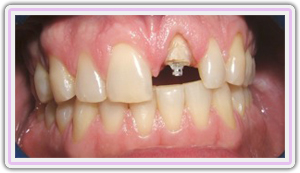

Fractured Tooth

Healing Screw On The Impant

Immediate Implant Placement